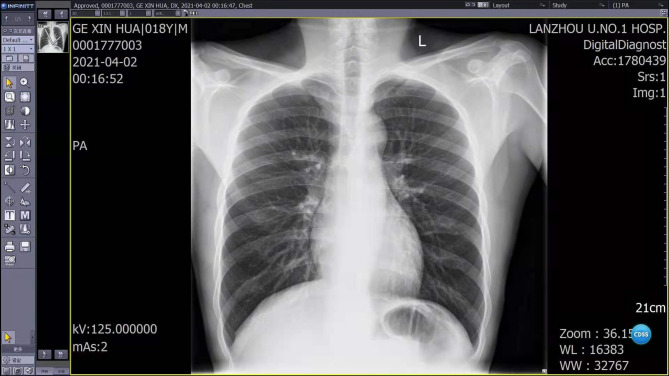

Case report: A young male patient presented with acute chest pain following strenuous exertion. Initial outpatient evaluation, including complete blood count (CBC), liver function tests (LFTs), renal function tests (RFTs), cardiac enzymes, and chest X-ray (CXR), yielded nondiagnostic results, leading to his discharge with analgesics. Three days later, during a national holiday when outpatient clinics were closed, the patient returned to the emergency department (ED) with persistent chest pain. A meticulous review of the initial CXR by the emergency physician revealed mediastinal widening (measuring 8.5 cm) and an abnormal contour of the aorta. Subsequent emergency computed tomography angiography (CTA) confirmed the diagnosis of a Stanford type B aortic dissection.